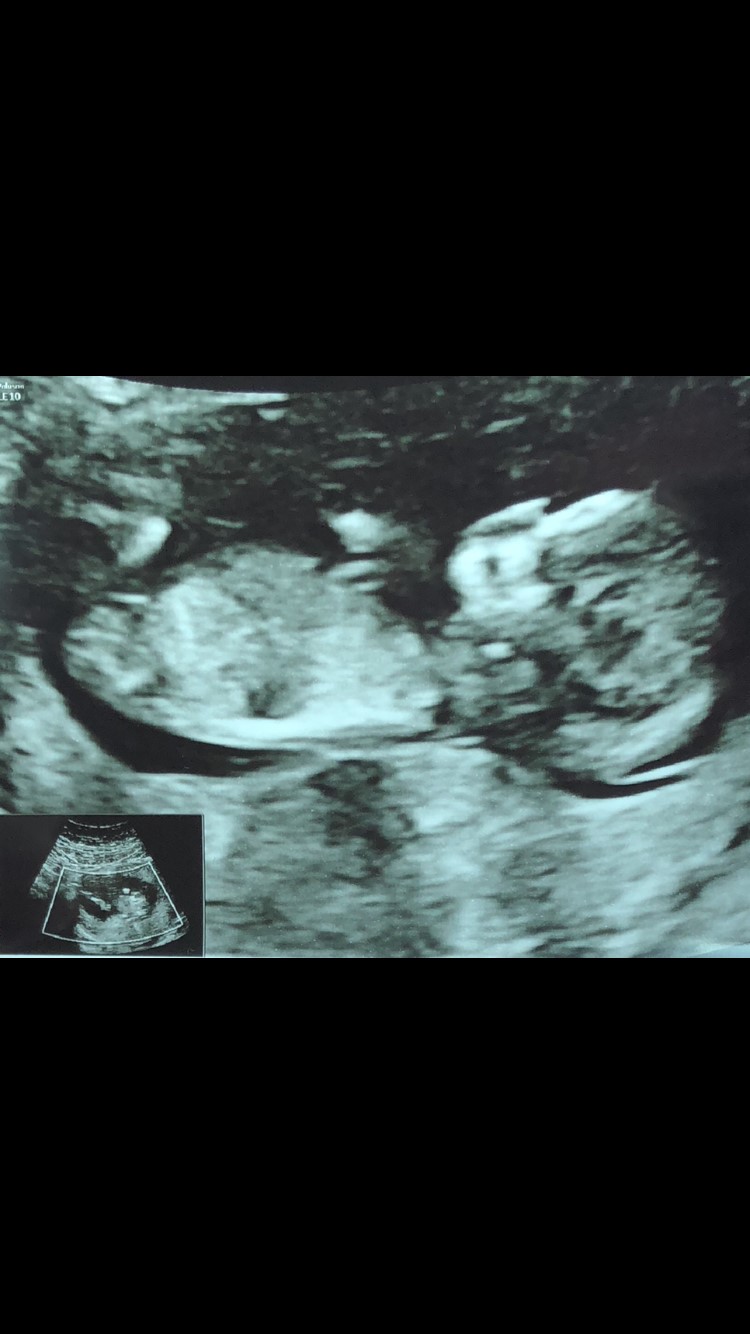

Nogen bud på kønnet? er 12+5

Pige